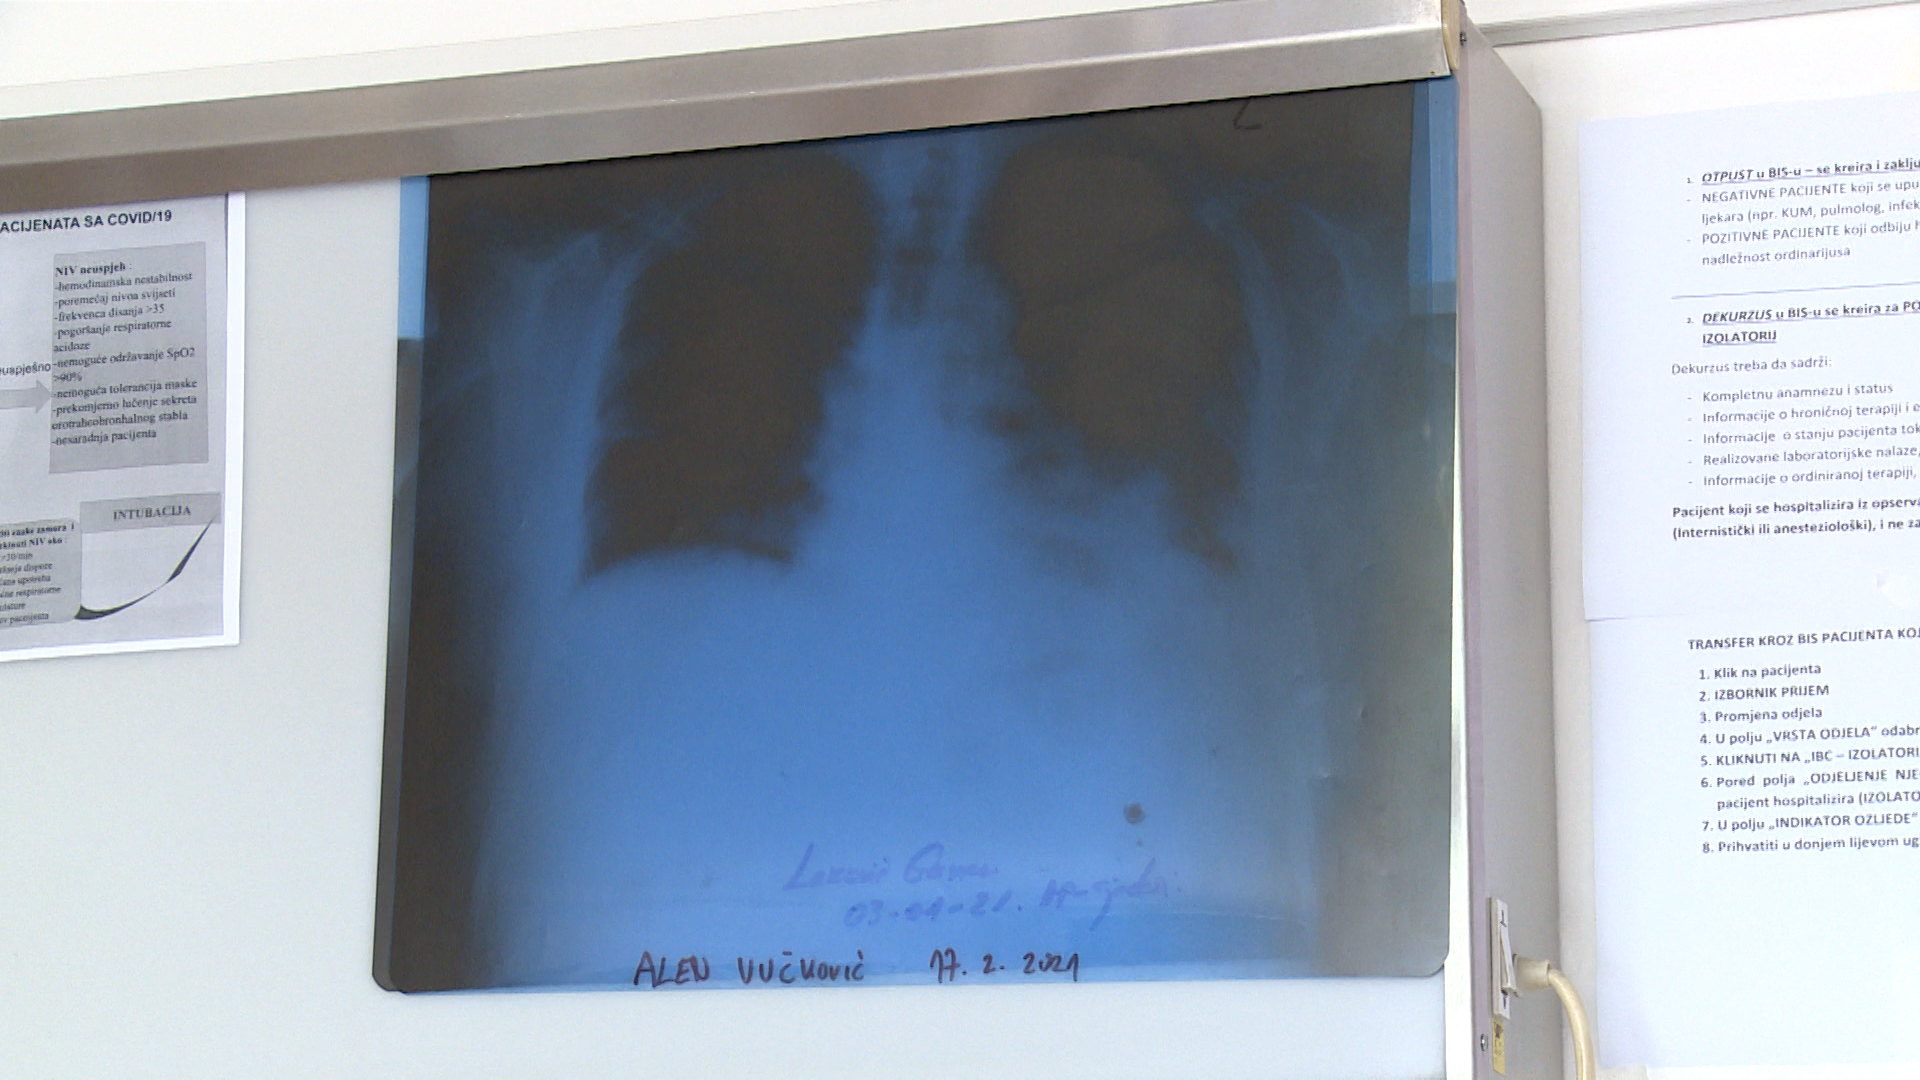

"Nakon godinu dana imao sam upalu pluća, danas mi je prvi radni dan. Najteže je kada dobijete teškog pacijenta za kojeg znate da mu je jako teško pomoći. To su pacijenti koji imaju tešku upalu pluća i zahtijevaju odmah respiratornu podršku. Apelujem na građane da se na vrijeme i što prije jave ljekaru, nakon prvih simptoma, povišene temperature, slabosti, kostobolje itd, i ne čekaju da se teško razbole. Covid pneumonija brzo napreduje. Znam da nije jednostavno pacijentima, lutaju, ne znaju kome se javiti. Moraju znati da se prvo jave ljekarima opšte prakse. Na osnovu kliničke slike koju procijeni, ljekar uputi će prema odgovarajućoj zdravstvenoj ustanovi", kazao doc. dr. Gojak.

Danas je na ovoj klinici 109 pacijenata. Pet će ih biti otpušteno kući, ali taj kapacitet će se popuniti već poslijepodne. Svi oni pacijenti koji više ne zahtijevaju kiseoničku podršku, bivaju otpušteni na kućno liječenje. Govoreći o najtežem slučaju, kazao je da ih je bilo više.

"Lično sam imao pacijente koji su mi umirali na rukama, vidite da se uguši pred vašim očima. Uključite sve mjere reanimacije, a ne možete pomoći. Najčešće se radi o trombu pluća, nekada srčanom zastoju", kazao je doc. dr. Gojak.